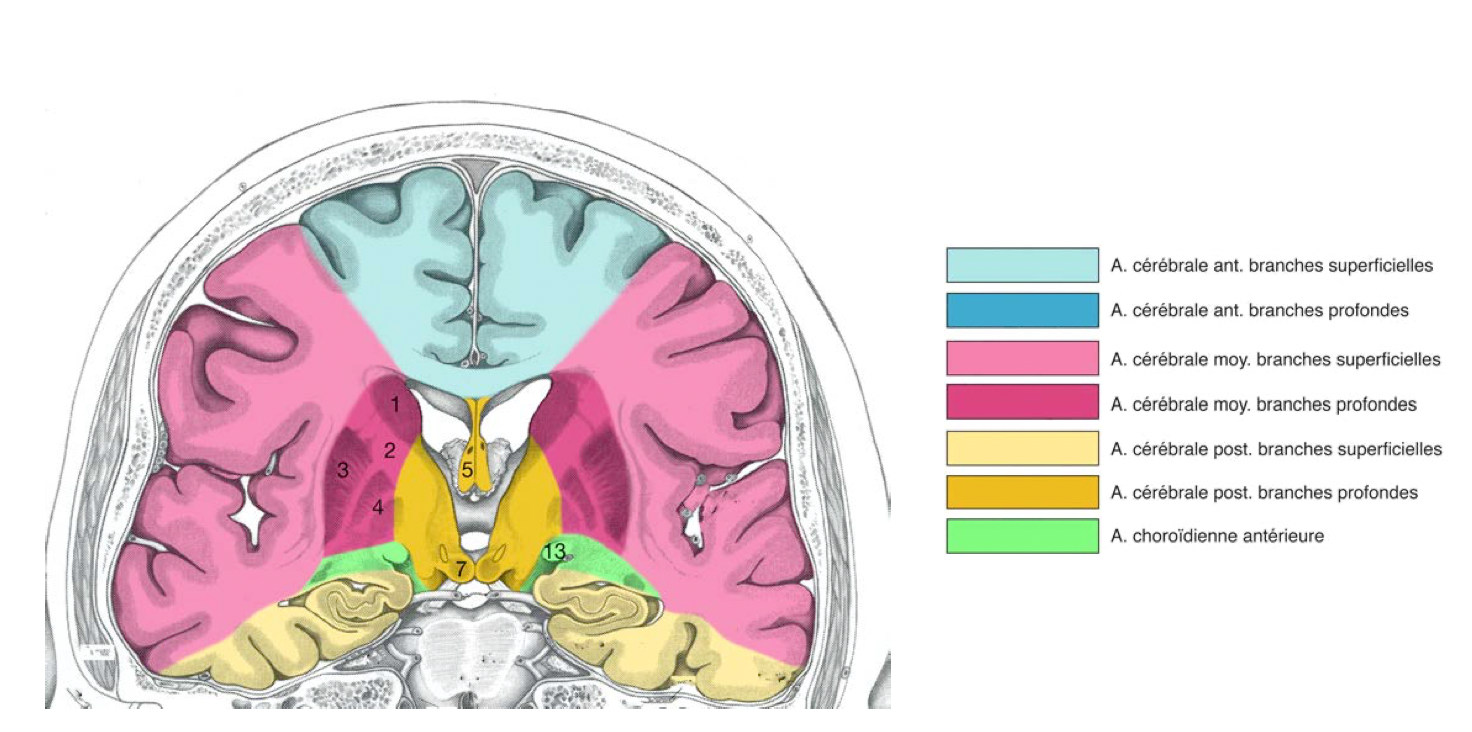

Score ASPECT

Le score ASPECT (Alberta Stroke Program Early CT Score) est un outil de quantification précoce de l’ischémie cérébrale. Le score est établi sur les lésions ischémiques détectées au scanner sans injection, un score à 10 étant normal et à 0 avec une ischémie totale dans la zone étudiée.

Le score est établi à partir de deux plans de coupes scanographiques axiaux standard :

• le premier passant par le thalamus et les noyaux lenticulaires ;

• le deuxième passant par les ventricules latéraux et adjacents au bord supérieur des ganglions de la base, de telle sorte que ceux-ci ne sont pas vus.

Entre ces deux plans de coupe, le territoire de l’artère cérébrale moyenne est divisé en 10 régions, chacune valant un point :

• 3 points sont attribués pour les structures sous-corticales ;

• 7 pour les parties corticales.

Un point est soustrait pour chaque région où l’on note un changement ischémique précoce :

• un score ASPECTS de 10 signifie un scanner normal ;

• un score ASPECTS de 0 signifie une ischémie diffuse à tout le territoire de l’ACM.

L’utilisation d’ASPECT est limitée au territoire de l’ACM. De ce fait, l’on ne peut pas y recourir pour l’infarctus de l’artère cérébrale antérieure ou vertébro-basilaire.